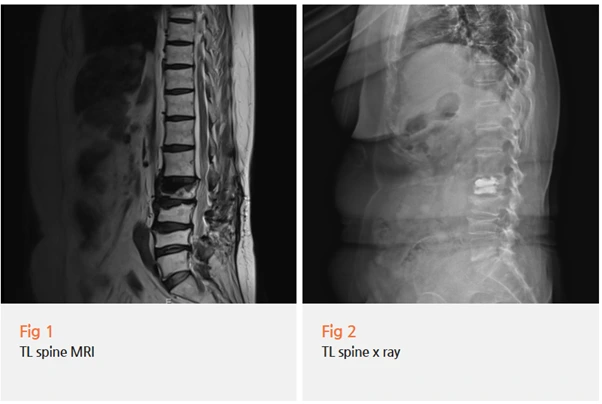

환자분께 뇌 MRI를 다시 촬영하고

추가 검사를 진행해보자고 말씀드렸습니다.

허리 치료는 잘 되고 있지만, 손떨림과 보행 장애는

별개의 원인이 있을 수 있다고 설명드렸어요.

뇌 MRI 재촬영과 함께 신경학적 검사를 종합적으로 시행했어요.

환자분의 증상 시작 시기와 진행 양상

떨림의 특징과 분포

근육 강직 정도

보행 패턴과 자세 변화

약물 반응 경과

이 모든 것을 세밀하게 평가한 결과, 파킨슨병으로 진단할 수 있었습니다.